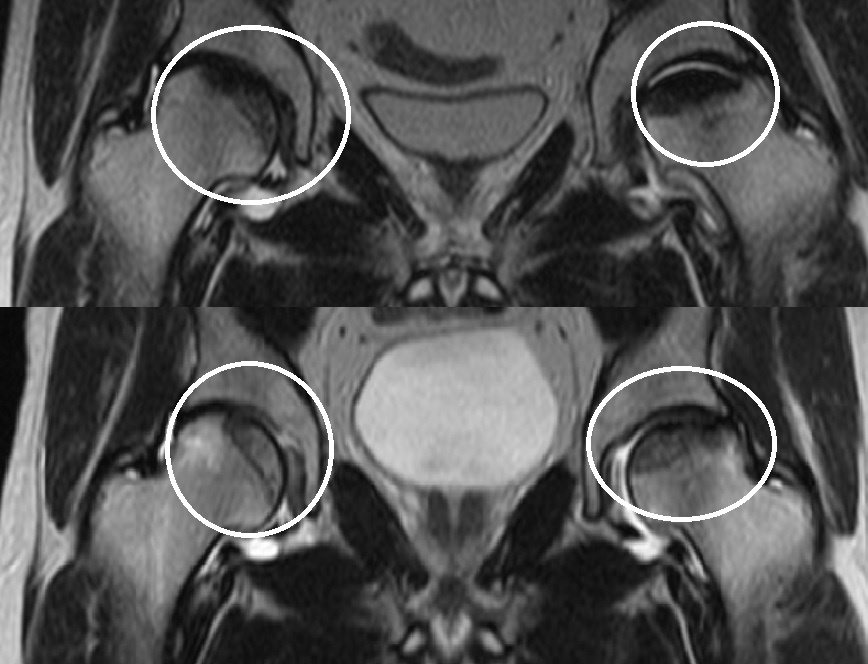

- Посмотрел. Все просто! У Вас асептическое воспаление в суставе - инфаркт кости.

На рентгене сморят форму кости и пока изменений формы нет, поскольку сустав еще не разрушен и там все по возрасту 1-2 степень.

На МРТ видно не только форму кости, но и то, что происходит внутри кости, а там произошел инфаркт кости, тот есть сосуд отвечающий за этот участок кости затромбирован и в кости без кровоснабжения развивается асептический невроз то есть кость растворяется и может разрушиться в этом в месте - месте асептического некроза (инфаркта кости).

Асептический некроз тазобедренного сустава с разрушением участка кости в течении года при несоблюдении охранительного режима - постельный режим или использование костылей